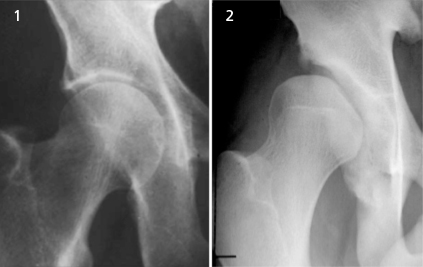

3. acetabulum의 깊이

그런데 이렇게 근육에 대한 고려 이전에 고민해야 할 것이 있습니다. 그것은 해부학적인 구조가 사람마다 다르다는 것입니다. 해부학적 변이에 대해서 우선적으로 생각할 것은 Hip socket depth입니다. 이런 해부학적 조직은 스트레칭되거나, 훈련되는 조직이 아닙니다.

4. acetabulum의 축

acetabulum이란 고관절 소켓에서 좌골에 움푹 들어간 부분입니다. 그런데 이 축의 문제가 있는 경우에도 충분한 힘을 낼 수 없습니다. 그림으로 우선 보겠습니다.

5. Femoral neck angle

고관절은 또한 수직상의 각도에 의해서도 영향을 받을 수 있습니다. 그러니까 만약 정말 운이 더럽게 없어서 얕은 hip socket에 retroversion된 acetabulum에 coxa valga femoral neck까지 있다면(...), 스쿼트의 깊이의 각도는 충분하지 않고 butt wink는 생길 수 밖에 없는 것입니다. 햄스트링이 단축되었냐 말았냐에 큰 상관이 없이 말이죠.